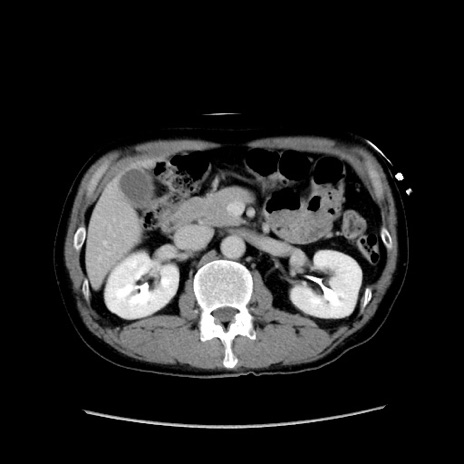

症例37(横断像)

冠状断像

【症例】40歳代 男性

【主訴】腹痛

【現病歴】4時間ほど前に電車に乗車中に臍部上より腹痛出現。徐々に増悪し起立困難となり、救急外来受診。生ものは数日食べていない。今朝お雑煮を食べた。

【身体所見】BT 36.8℃、BP 117/84mmHg、HR 91/min、SpO2 97%、苦悶様、腹部:臍上部広範囲圧痛あり、反跳痛±

【データ】WBC 8100、CRP 0.03